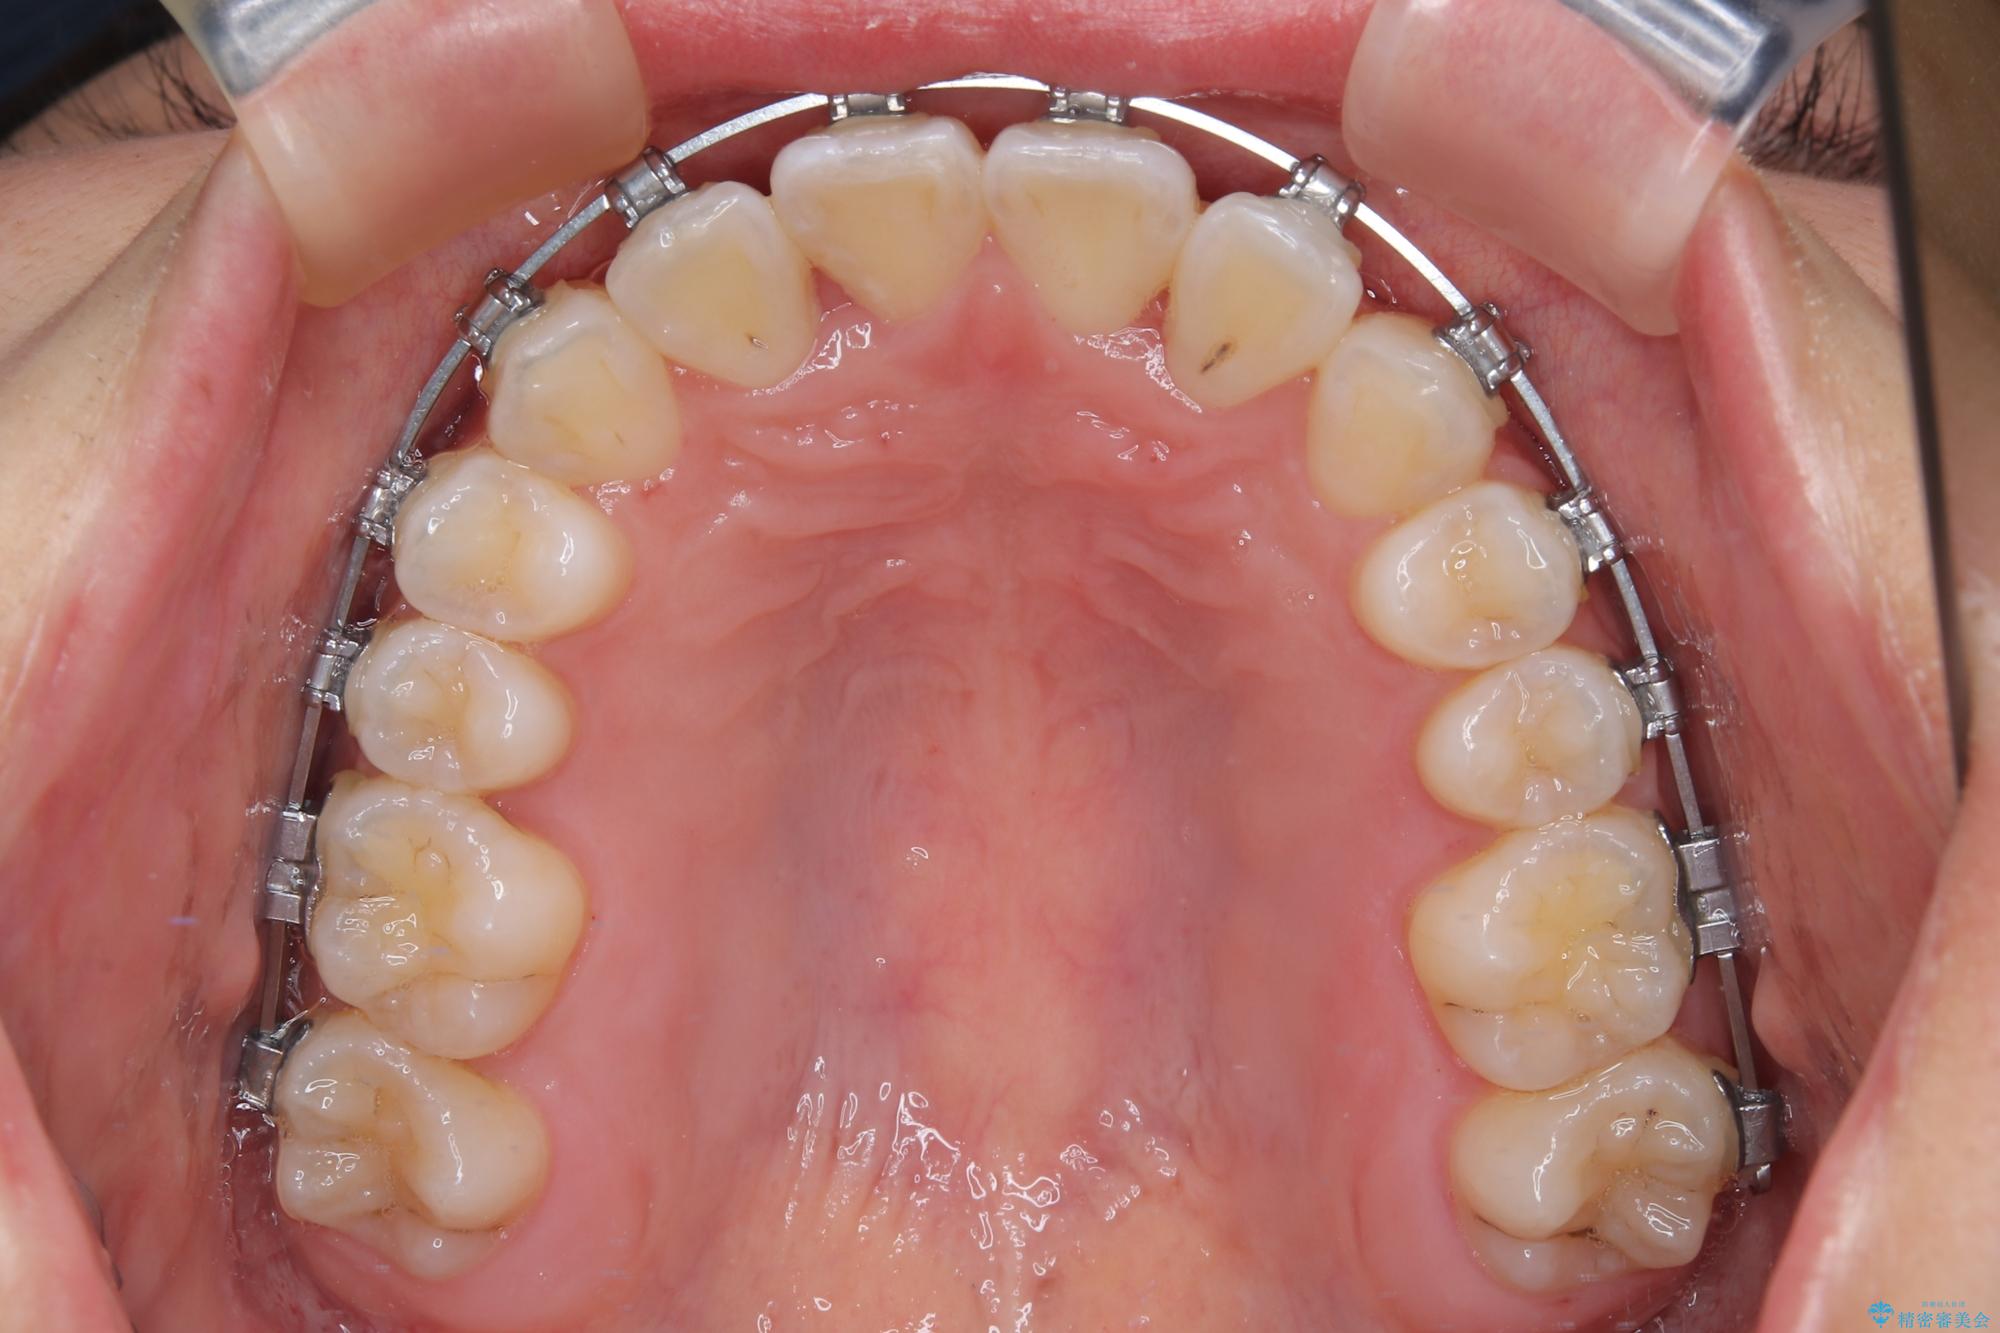

前歯のクロスバイト 裏側に隠れた歯をワイヤー装置で短期間治療

- 上顎前歯のクロスバイトを気にして来院された患者様です。

装置の外見を気にしていましたが、短期間で治療を終えることができるだろうと伝えると、安価であるメタルブラケットを選択されました。

想定通り、1年強で綺麗に仕上げることができました。